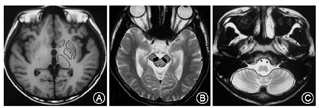

选取苍白球、尾状核头、壳核、丘脑、小脑、黑质6个感兴趣区(ROI)。ROI的设置由两位不知道分组情况的神经影像学医师进行(图1)。各个感兴趣区在显示最清楚的层面固定位置进行选取。分别测量各感兴趣区ADC值、FA值以及弥散张量矩阵的三个特征值λ1、λ2、λ3。

通过独立样本t检验,肝脑型患者多个核团、核团纤维、核团之间联系纤维DTI数据差异有统计学意义(表2,图2)。